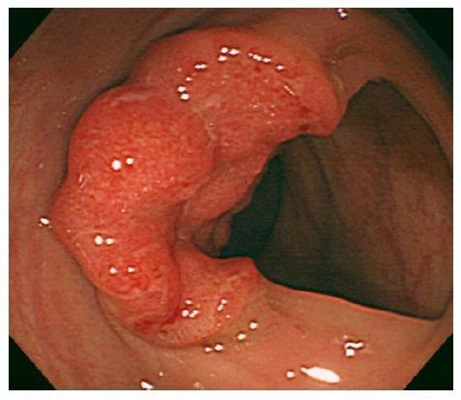

直腸癌圖片